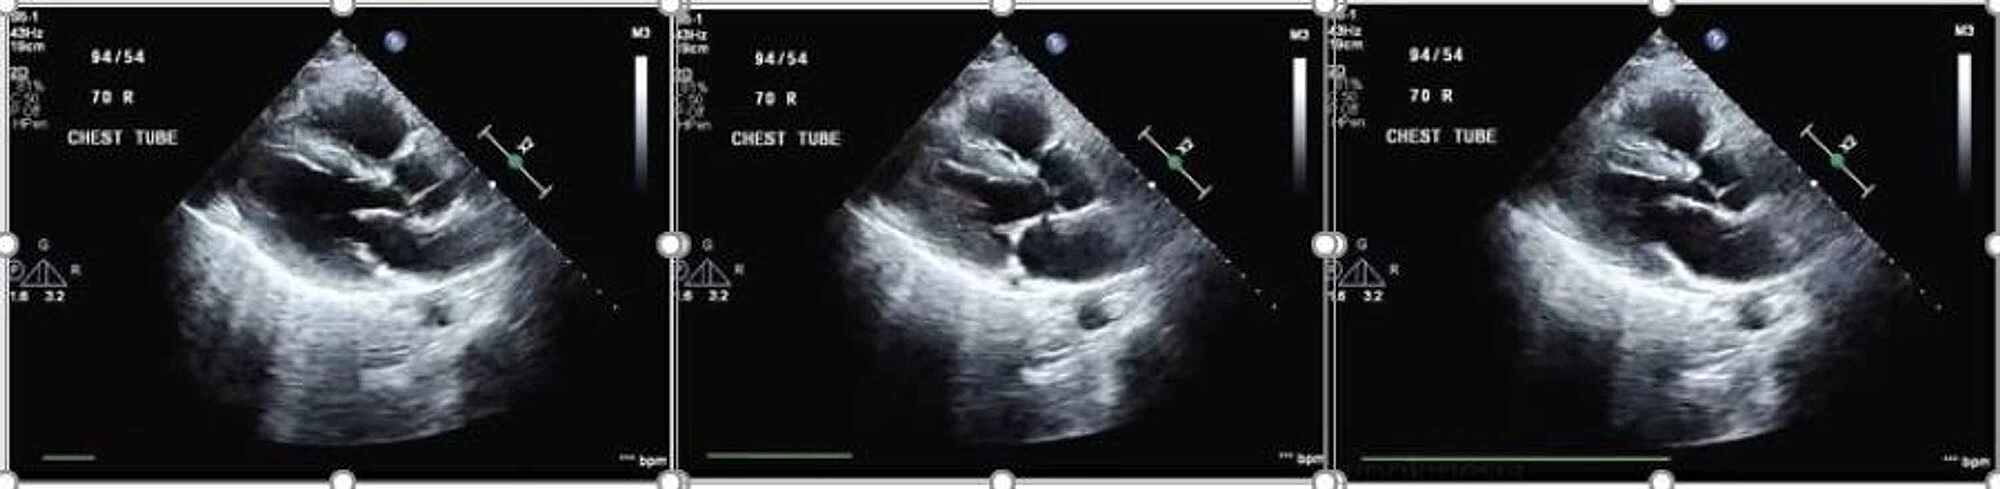

On arrival to hospital 2, he underwent immediate cannulation for femoro-jugular VV-ECMO and was started on an initial flow rate of 4100 ml/min, gas sweep of 11 L/min, goal oxygen saturation (SaO2) > 85% and PaO2 > 55 mmHg. He was also started on inhaled nitric oxide (iNO) at 20 ppm. Sedation and neuromuscular blockade were continued. A five-day course of dexamethasone (20 mg IV once daily) was given as well. A transthoracic echocardiogram demonstrated mild right ventricular dilation with hypokinesia of the mid-right ventricular free wall and left ventricular ejection fraction of approximately 60% (Figure 3).